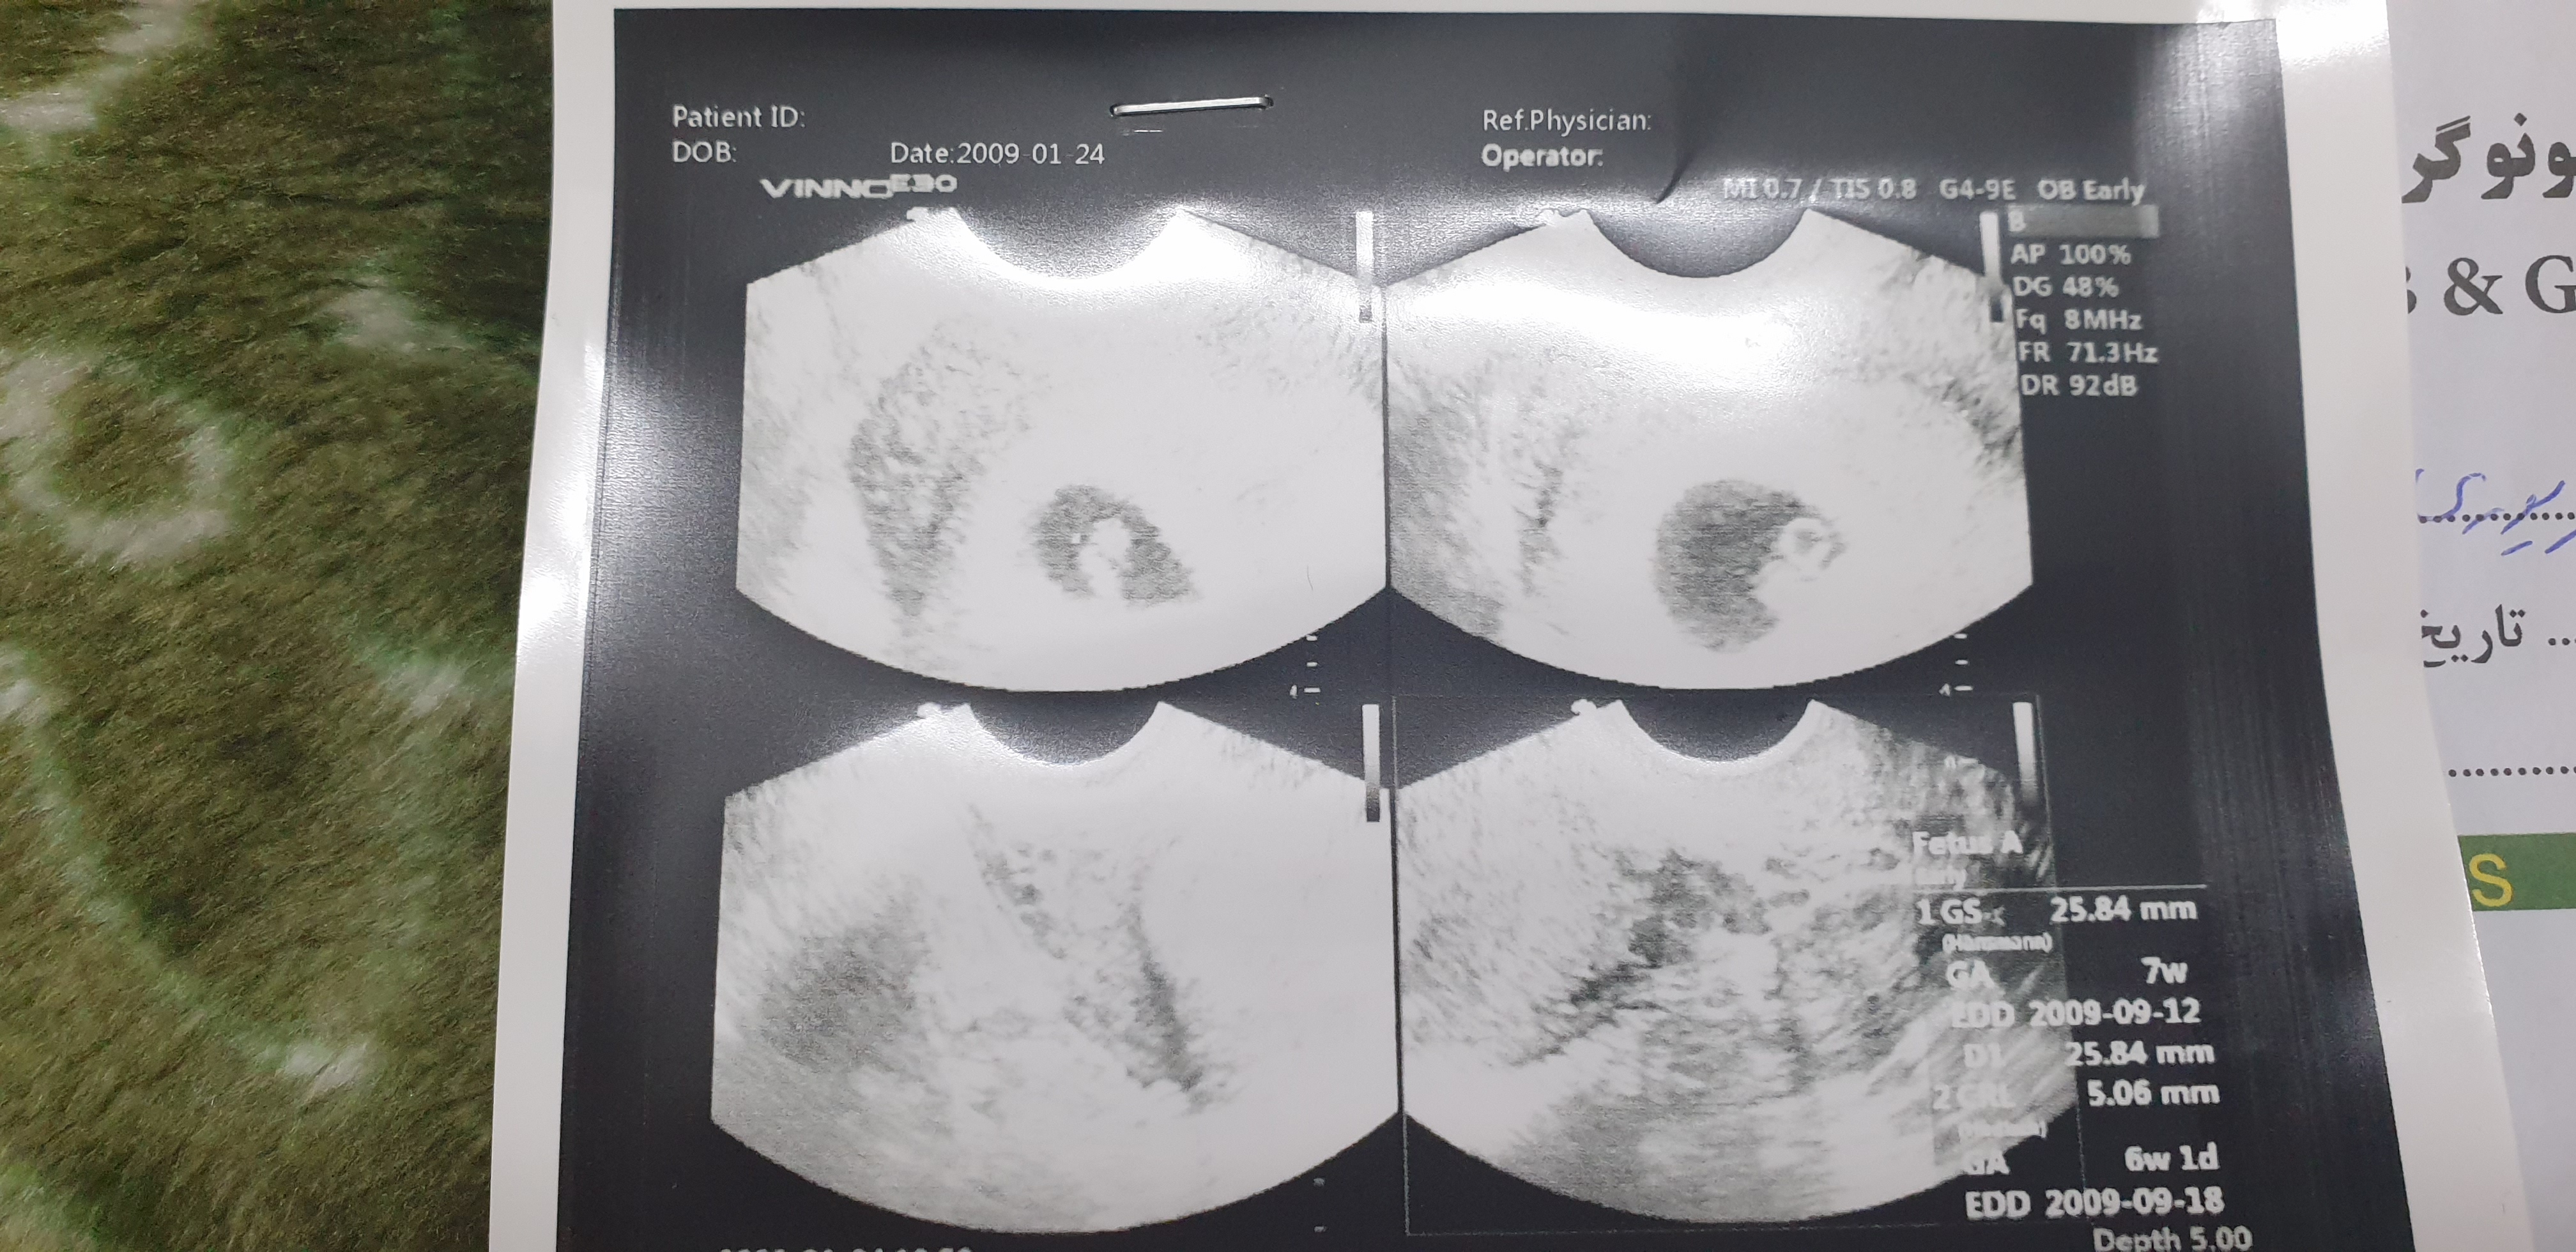

تشخیصش که خیلی سخته ولی من سونو ۸هفته گذاشتم یه خانومی گفتن چون جنین کشیده هست و شبیه لوبیاس پسره ...

به دوستمم گفتن ک دختره و درست هم بود .اونم از نشستن جنین متوجه شده

من دكترم از سونوي ١٢ هفته متوجه نشد و احتمال داد بعد شما توقع داري ني ني سايتي ها از سونوي هفت ...